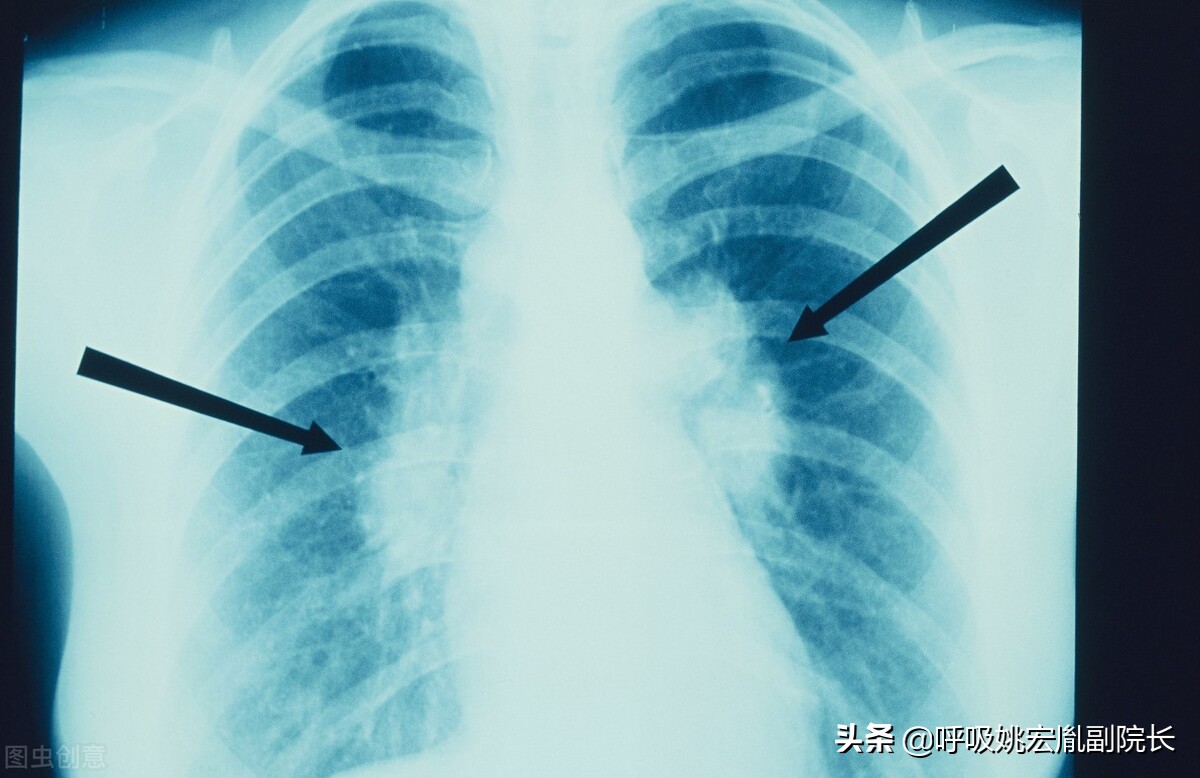

肺结节:肺结节是指在肺实质内而不属于正常肺组织的结节状阴影,直径小于3厘米,其中直径小于1厘米的称之为小结节,直径小于3毫米的称之为微结节,而大于3厘米的我们称之为肿块。肺结节可以表现为单独一个,也可以是多个。80%-90%以上的肺结节都是良性的,当然也有一部分结节是恶性的,而少数肺良性结节在随访的过程中可能会出现恶变。